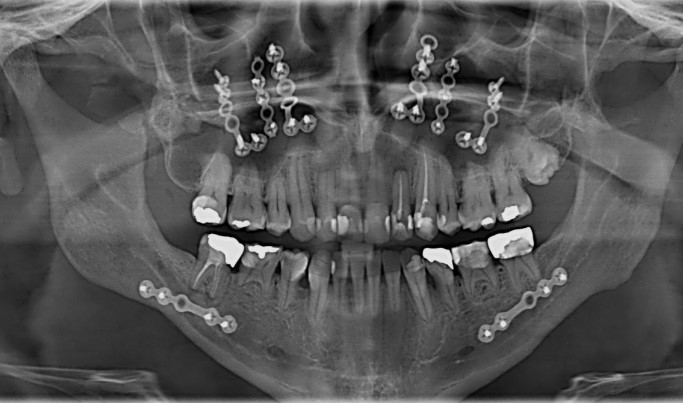

Большую роль играет диагностический этап. Перед операцией пациент в обязательном порядке проходит расширенное обследование: 3D-компьютерная томография, фотометрический анализ лица, функциональные тесты. Выбор методов диагностики и используемое оборудование напрямую сказываются на стоимости лечения. Многие клиники предлагают комплексные пакеты, в которые входят консультации, анализы, моделирование результата и планирование с помощью цифровых технологий.

Используемые материалы также влияют на формирование прайса. В современной стоматологии применяются высокотехнологичные сплавы, мини-пластины и винты для фиксации челюстей, которые варьируются по стоимости в зависимости от производителя и класса. Клиники, сотрудничающие с ведущими поставщиками медицинских материалов, формируют прайс с учётом качества и надёжности компонентов.

Использование инновационных технологий. Применение 3D-планирования, навигационных систем, компьютерного моделирования увеличивает стоимость, но минимизирует риски и повышает точность результата. В Алматы ряд клиник внедряет эти методики для прогнозируемого и безопасного лечения.

Главной тенденцией становится широкое внедрение цифровых технологий. Компьютерная томография высокого разрешения, 3D-моделирование, виртуальное планирование операции – всё это позволяет точно прогнозировать результат и сократить время самой операции. Использование CAD/CAM-технологий обеспечивает высочайшую точность изготовления хирургических шаблонов и фиксаторов, что заметно сказывается на безопасности и эстетике итогового результата.